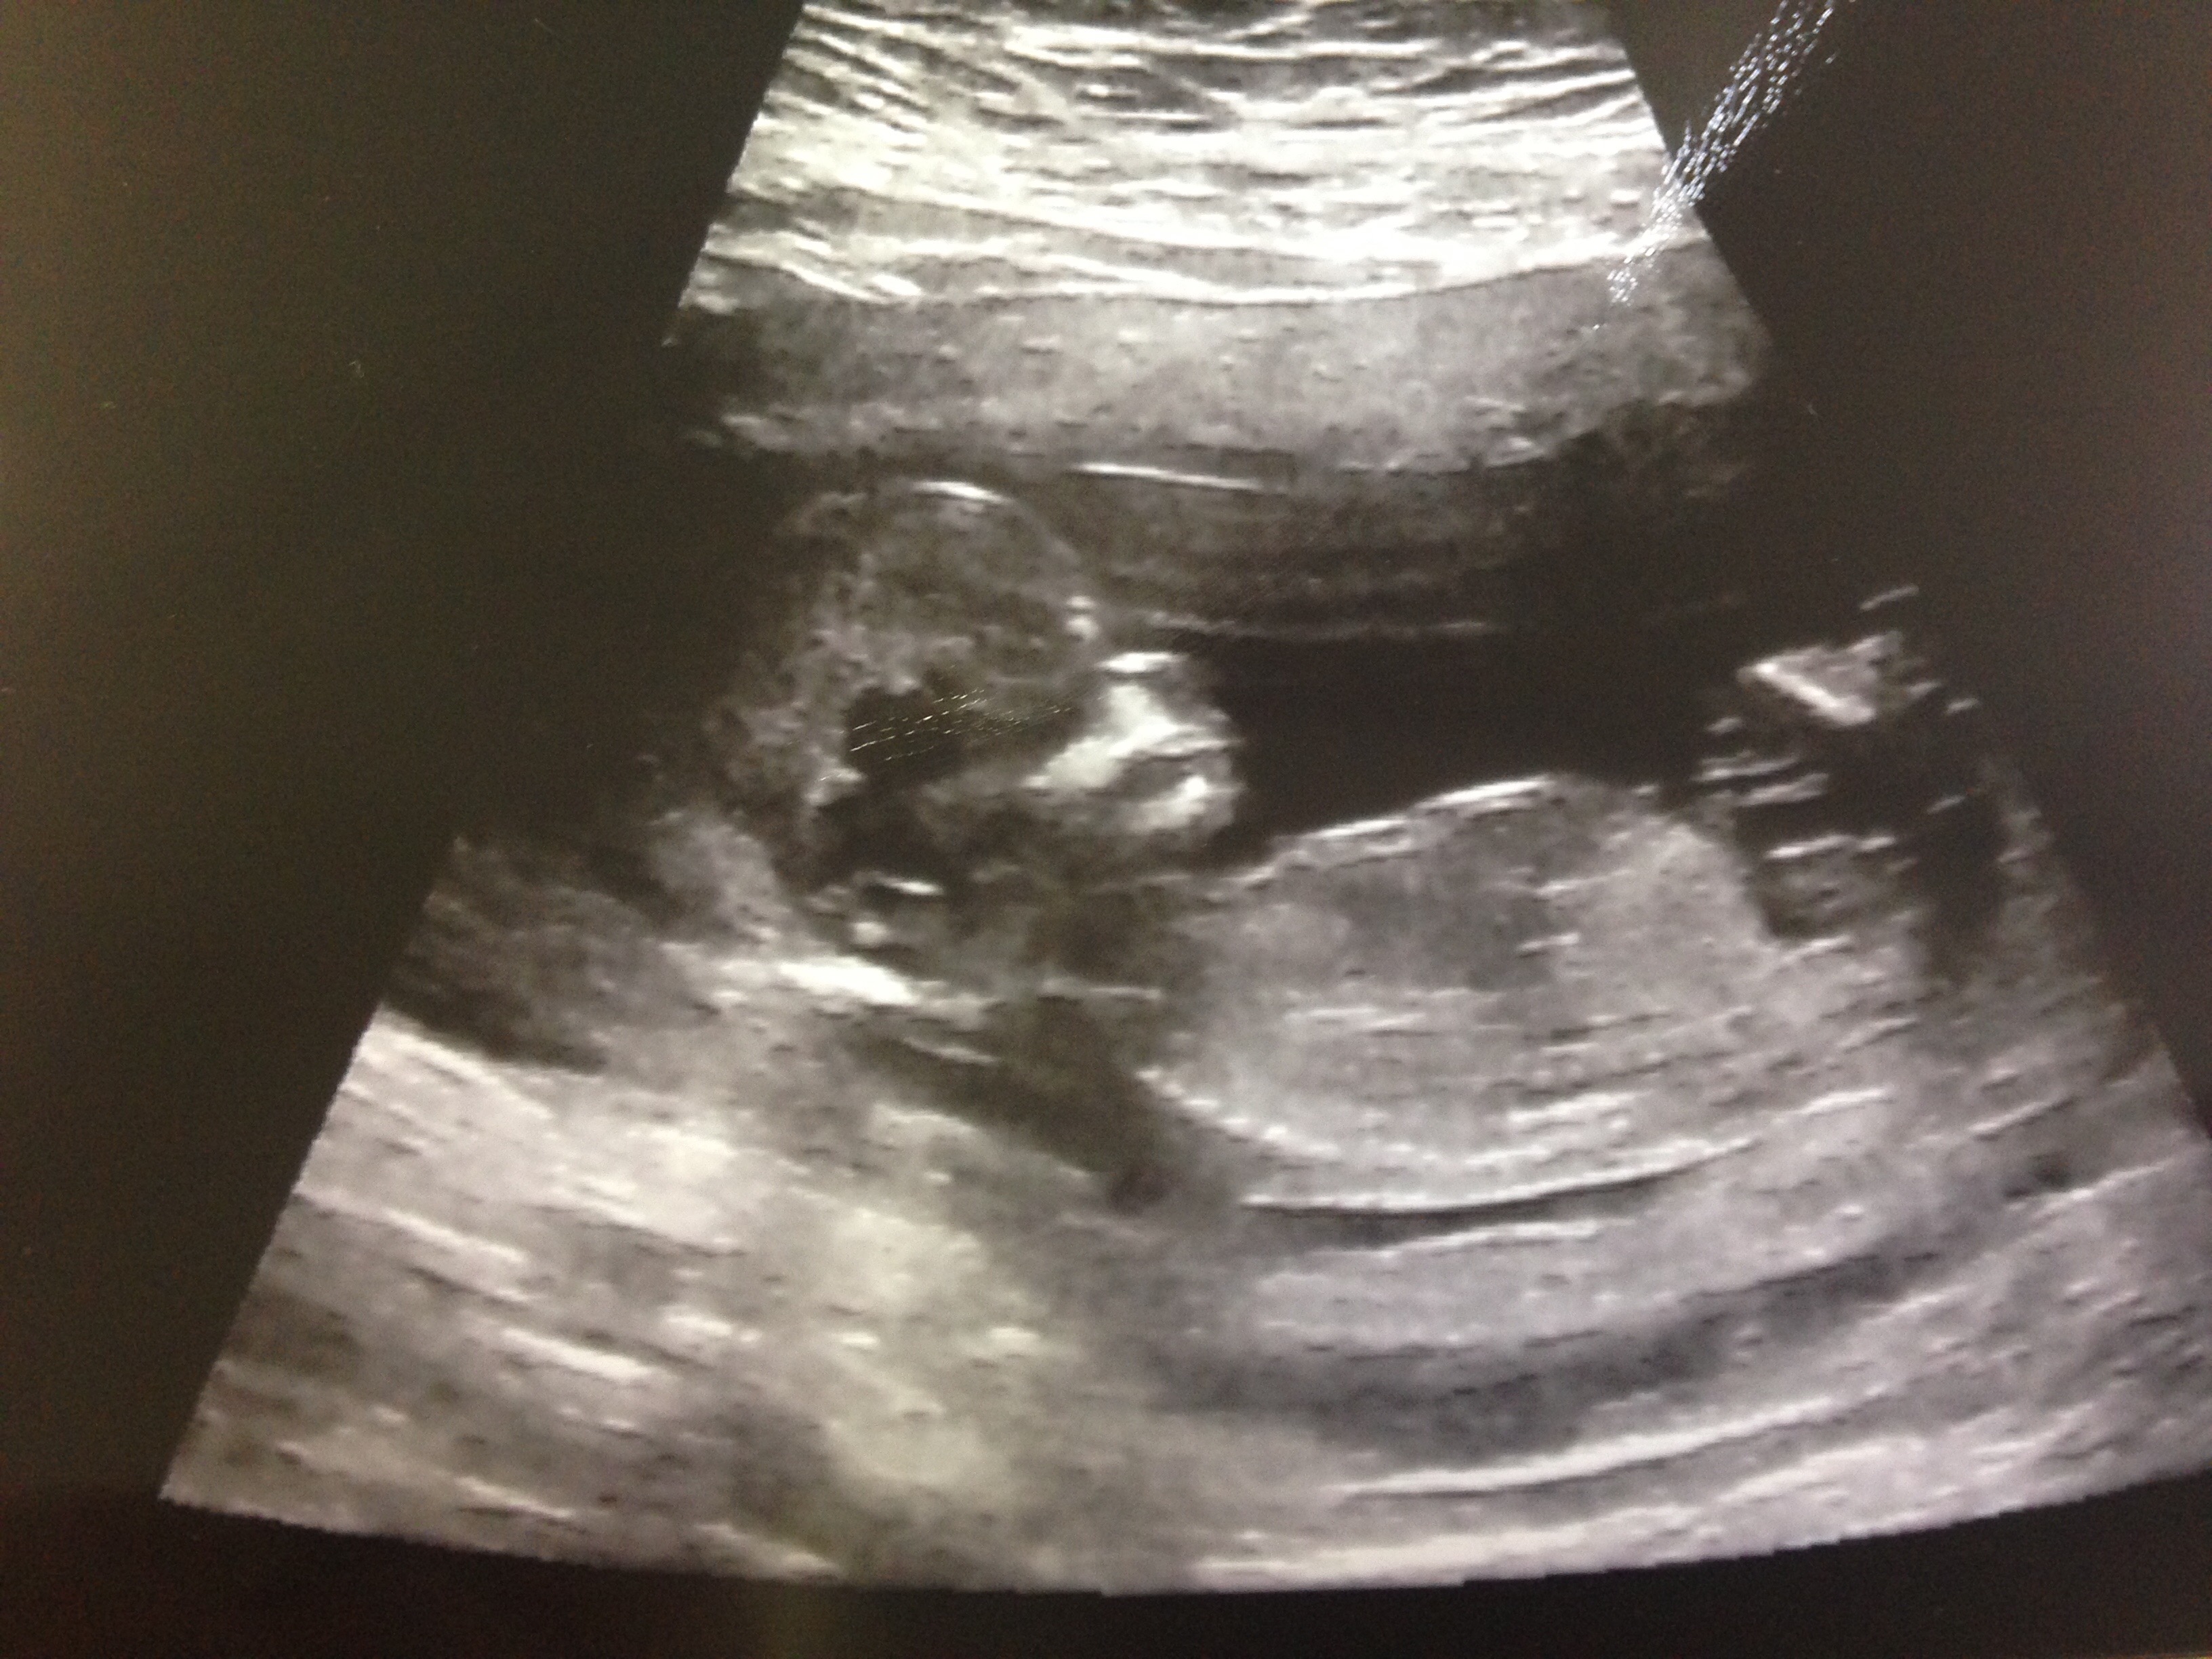

This photo was taken at our 13w2d ultrasound. Please take a guess regarding gender! Attachment 31452

Don't know if I can see a clear nub, but tentatively leaning pink

Maybe girl if that's the nub I'm seeing.

thinking girl BUT the nub is wierdly quite high ?!